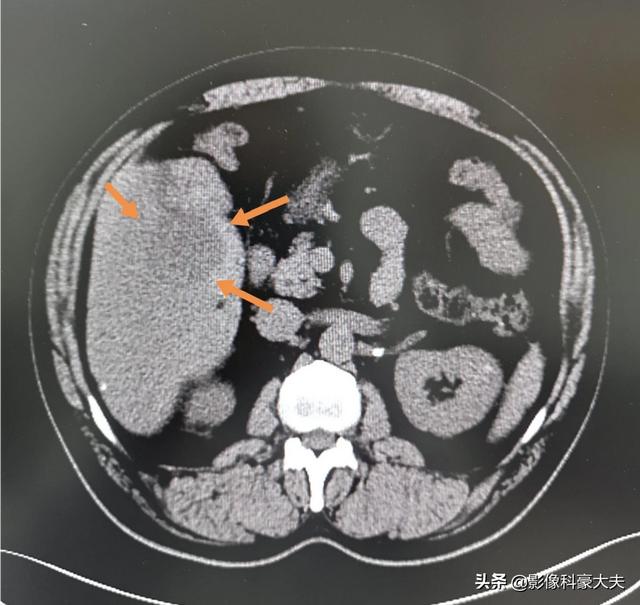

Il s'agit d'un patient atteint d'hépatite B chronique. L'examen physique a révélé un petit cancer du foie. S'il n'est pas opéré à temps, il évoluera vers un stade avancé en 6 mois au maximum. Grâce à un équipement moderne de pointe, ce patient a été découvert et opéré à temps, et cela fait plus d'un an qu'il n'y a pas eu de récidive :